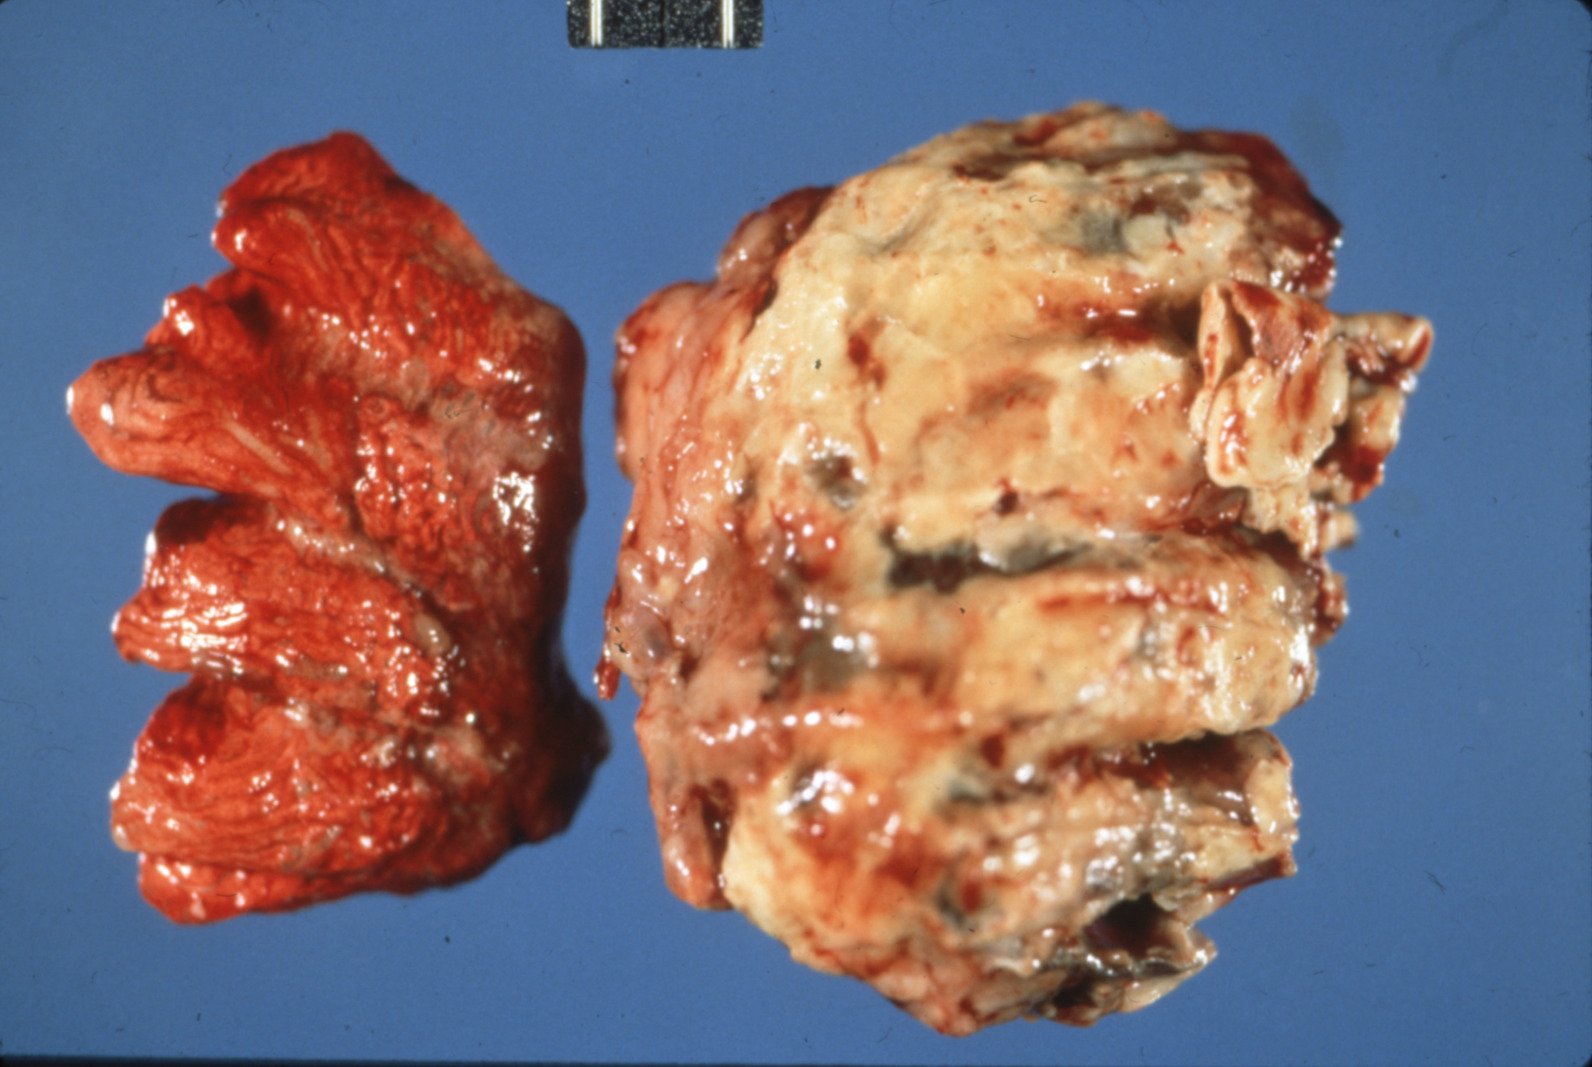

Fowl cholera (slide study set no. 19) Item Info

Fowl cholera (slide study set no. 19)

Poultry--Diseases Chicken cholera

Slide Study Set #19, Fowl Cholera (includes 25 color slides), undated